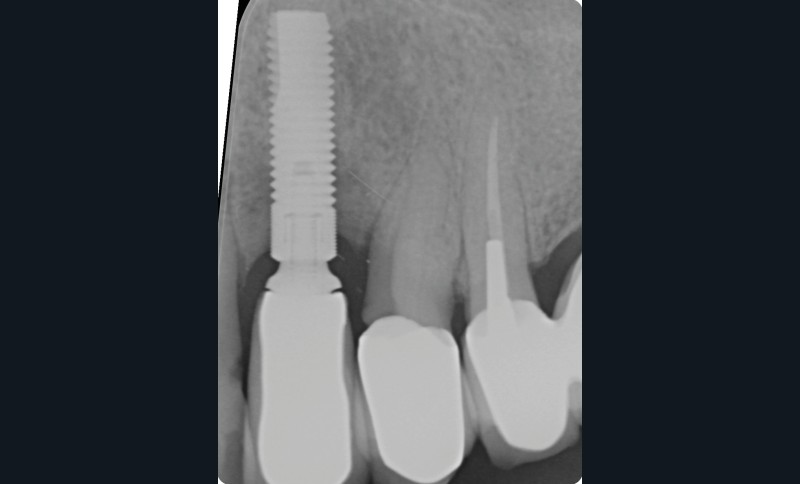

L’implant

- Site 23

- Mis en place il y a 12 ans